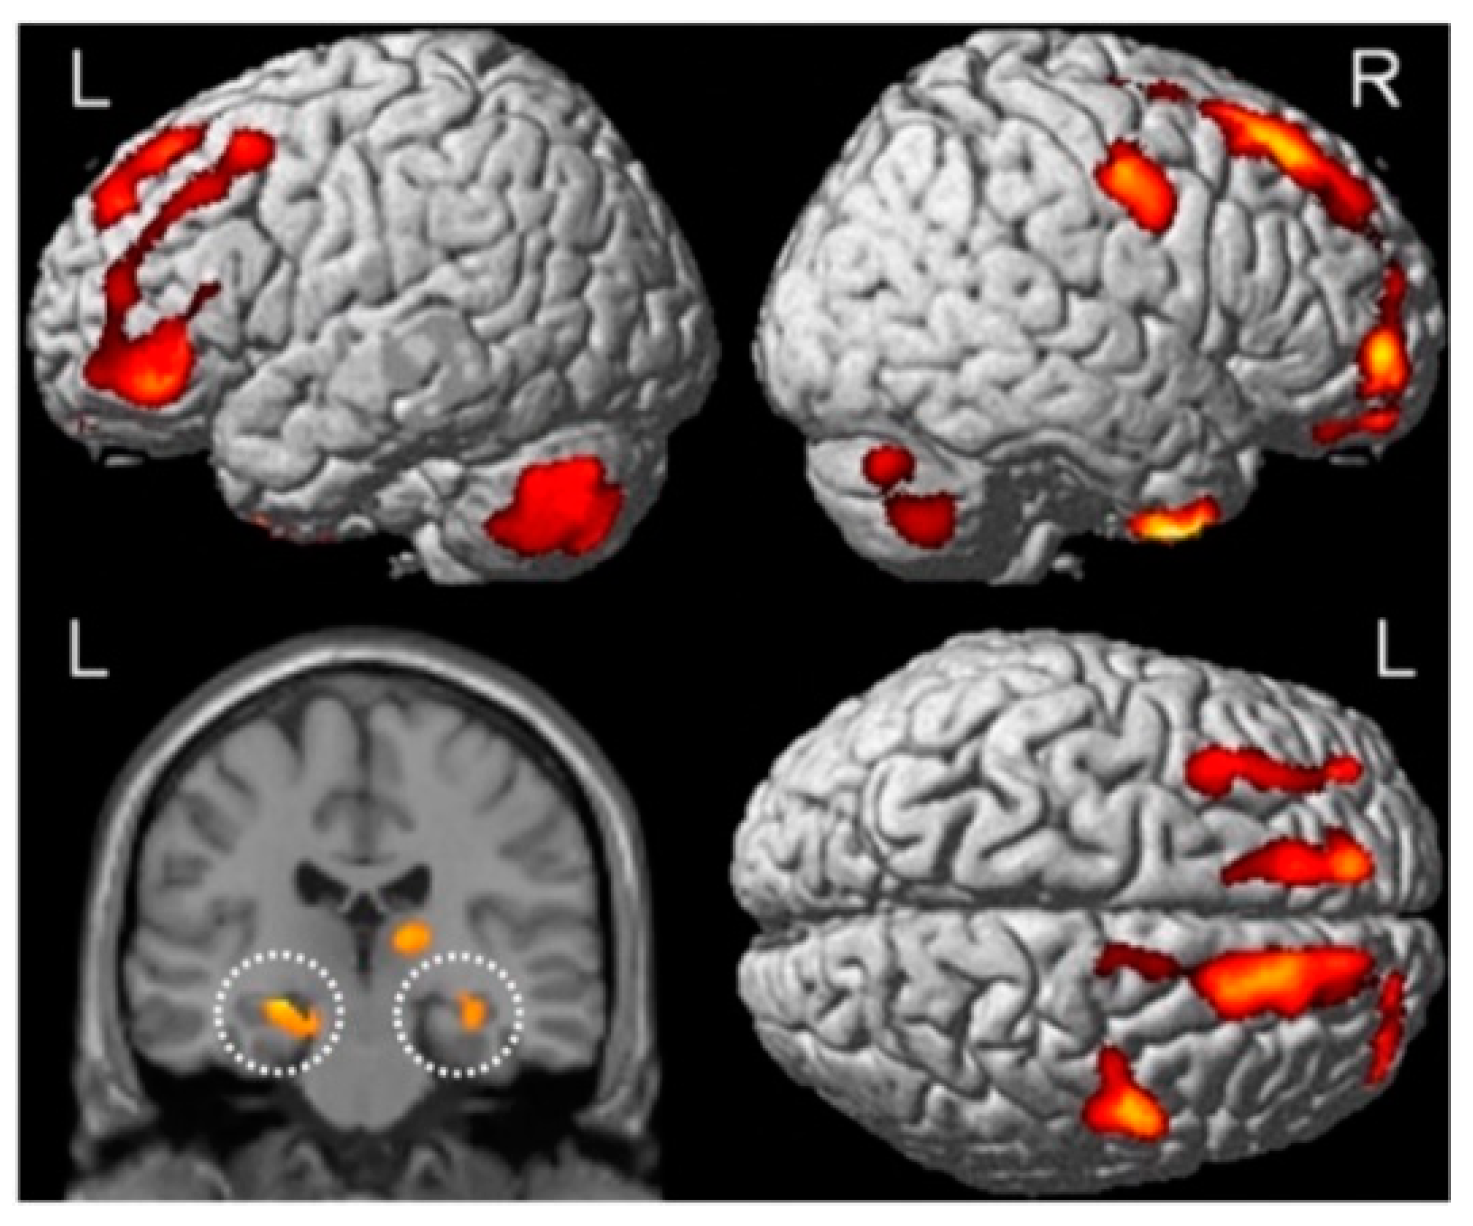

- Sekeres, M.J.; Winocur, G.; Moscovitch, M.; Anderson, J.A.E.; Pishdadian, S.; Martin Wojtowicz, J.; St-Laurent, M.; McAndrews, M.P.; Grady, C.L. Changes in Patterns of Neural Activity Underlie a Time-Dependent Transformation of Memory in Rats and Humans. Hippocampus 2018, 28, 745–764. [Google Scholar] [CrossRef] [PubMed]